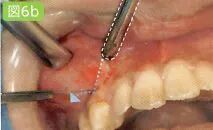

吸引针刺部位溢出的麻醉药物

虚线部分为吸唾管